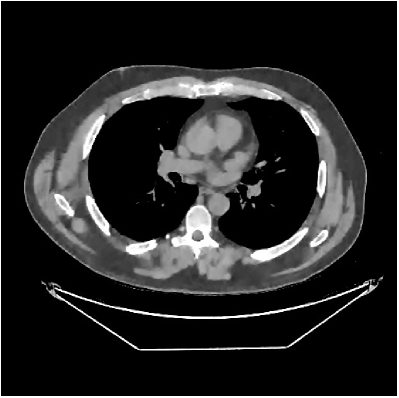

This section compares the reconstruction quality and runtime among the proposed MBIR method, PWLS-ST-, and other three MBIR methods, PWLS-EP, PWLS-DL, and PWLS-ST-. Table I shows that, for both 2D and 3D sparse-view CT reconstructions of the XCAT phantom, the proposed PWLS-ST- model outperforms PWLS-EP and PWLS-ST- in terms of RMSE. In addition, PWLS-ST- using a square transform (of size ) achieves lower RMSE than PWLS-DL using an overcomplete dictionary (of size ) for 2D sparse-view reconstructions. Fig. 3(a) and Fig. 4 show the reconstructed images for 2D and 3D phantom experiments, with different reconstruction models and different number of views. (See the corresponding error maps in the supplement.) The proposed PWLS-ST- consistently gives more accurate image reconstructions compared to other MBIR methods. Specifically, PWLS-ST- has smaller errors in the heart region (see zoom-ins in Fig. 3(a)) of 2D reconstructions than PWLS-DL and PWLS-ST-. In addition, compared to PWLS-ST-, PWLS-DL and PWLS-ST- have some ringing artifacts around the edges with high transition, e.g., edges between air and soft tissues. (See a comparison of profiles of PWLS-ST- and PWLS-ST- in the supplement.) In particular, PWLS-ST- and PWLS-DL give more visible ringing artifacts for 2D reconstruction from fewer views, and PWLS-ST- has these ringing artifacts for 3D reconstructions regardless of the number of views (see zoom-ins in Fig. 4). Table II reports runtimes of different MBIR methods in reconstructing the -views XCAT phantom scan. (FBPConvNet is a non-MBIR method and its runtime for processing a image is approximately one second with a TITAN Xp GPU.) While providing better reconstruction quality, the proposed Algorithm 1 of PWLS-ST- has shorter runtime compared to the algorithms of PWLS-DL and PWLS-ST- in Section III-A. Similar to the PWLS-EP algorithm, the reconstruction time of the PWLS-DL, PWLS-ST-, and PWLS-ST- algorithms can be further reduced by using ordered subsets [51].

Fig. 3(b) shows that when tested on the clinical scan data, the proposed PWLS-ST- method improves reconstruction quality in terms of noise and artifacts removal (e.g., see zoom-ins for soft-issue regions), and edge preservation (e.g., see zoom-ins for bone regions), compared to PWLS-EP and PWLS-ST-. Compared to PWLS-DL, PWLS-ST- achieves comparable image quality, but requires less computational complexity.

![]() |

| (a) 2D fan-beam CT experiments |

| (b) 3D axial cone-beam CT experiments |